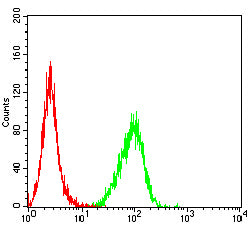

分类: 科研抗体货号: 31953别名:应用: FCM反应种属: Human